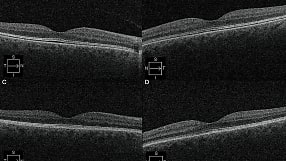

A Case of Cystoid Macular Edema Associated With Maintenance-dose Ozanimod

This case report will discuss asymptomatic CME in the maintenance period of ozanimod use for moderate to severe ulcerative colitis.

By Jeffrey Bloom, DO, Caleb Liles, DO, Jacob Brucker, DO, et al.